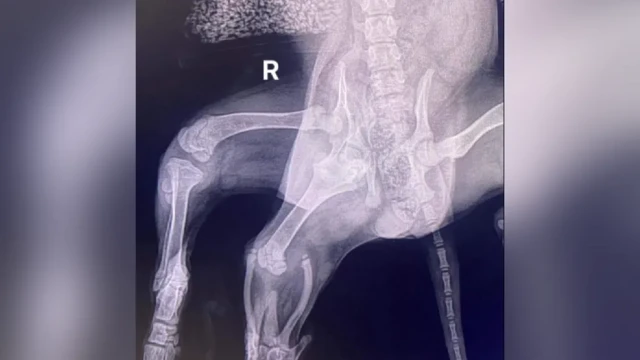

Ariel, di six-legged dog wey dem find for supermarket car park, don do surgery to remove her extra limbs.

Surgeon Aaron Lutchman manage to save all four of her working limbs afta im bin fear say dem fit amputate one.

"Di vet wey initially assess Ariel note say, in addition to her two surplus back legs, she get additional vulva," di 42-year-old tok.

Im add say CT scan later reveal say she only get one kidney, wey increase di complexity of di medical treatment she require.

"And, Ariel pelvis neva form properly, sake of say she get two hip joints on one side.

"As a result her normal back right leg virtually no get muscle tone, so possibility dey say dem fit comot.

"Tankfully say no be di case though as e dey show signs say e don strengthen dis recent months."